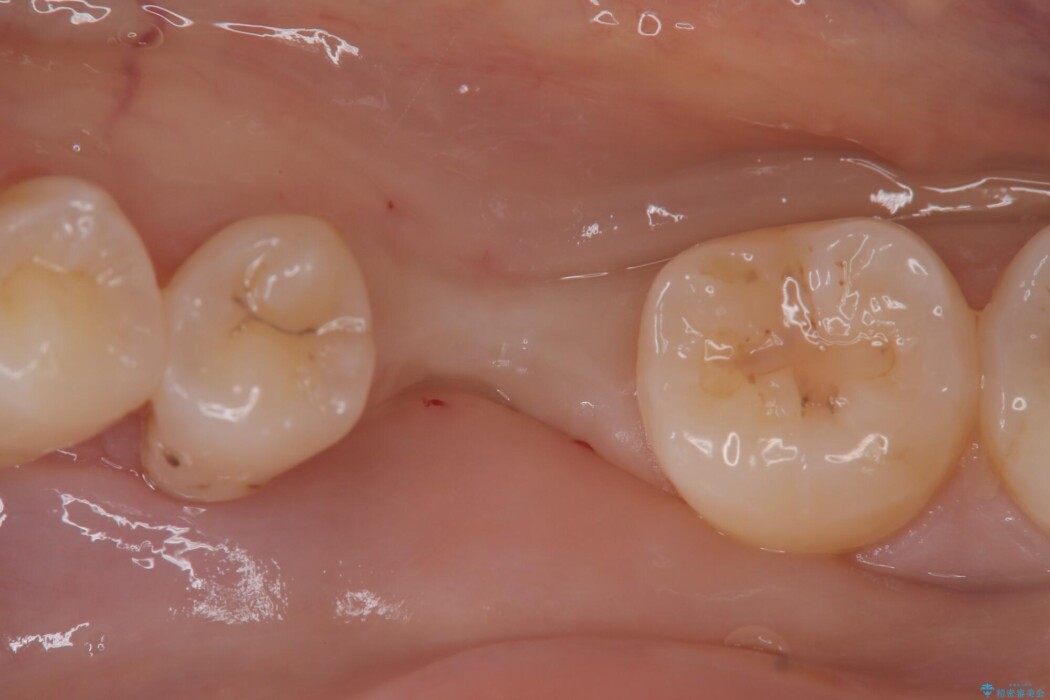

左下奥歯の抜歯後、長期間放置していたために、周囲の骨が吸収してしまいました。 特に垂直的な高さが不足しており、通常の術式ではインプラント埋入が難しい状態でした。

精密検査の結果、高さに制限はあるが厚みは十分に確保されていることが確認されました。

骨を増やす治療は行わず、残っている骨を最大限に活用し治療を行うこととしました。

一般的に、骨が少ない場所への埋入は高度な技術を要しますが、今回は適切なサイズ(8.5mm)を選択し、埋入する深さを緻密にコントロールすることで、周囲の神経や重要な組織を傷つけることなく安全に処置を完了しました。